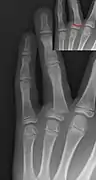

Salter–Harris III fracture of big toe proximal phalanx.

Salter–Harris IV fracture of big toe proximal phalanx.